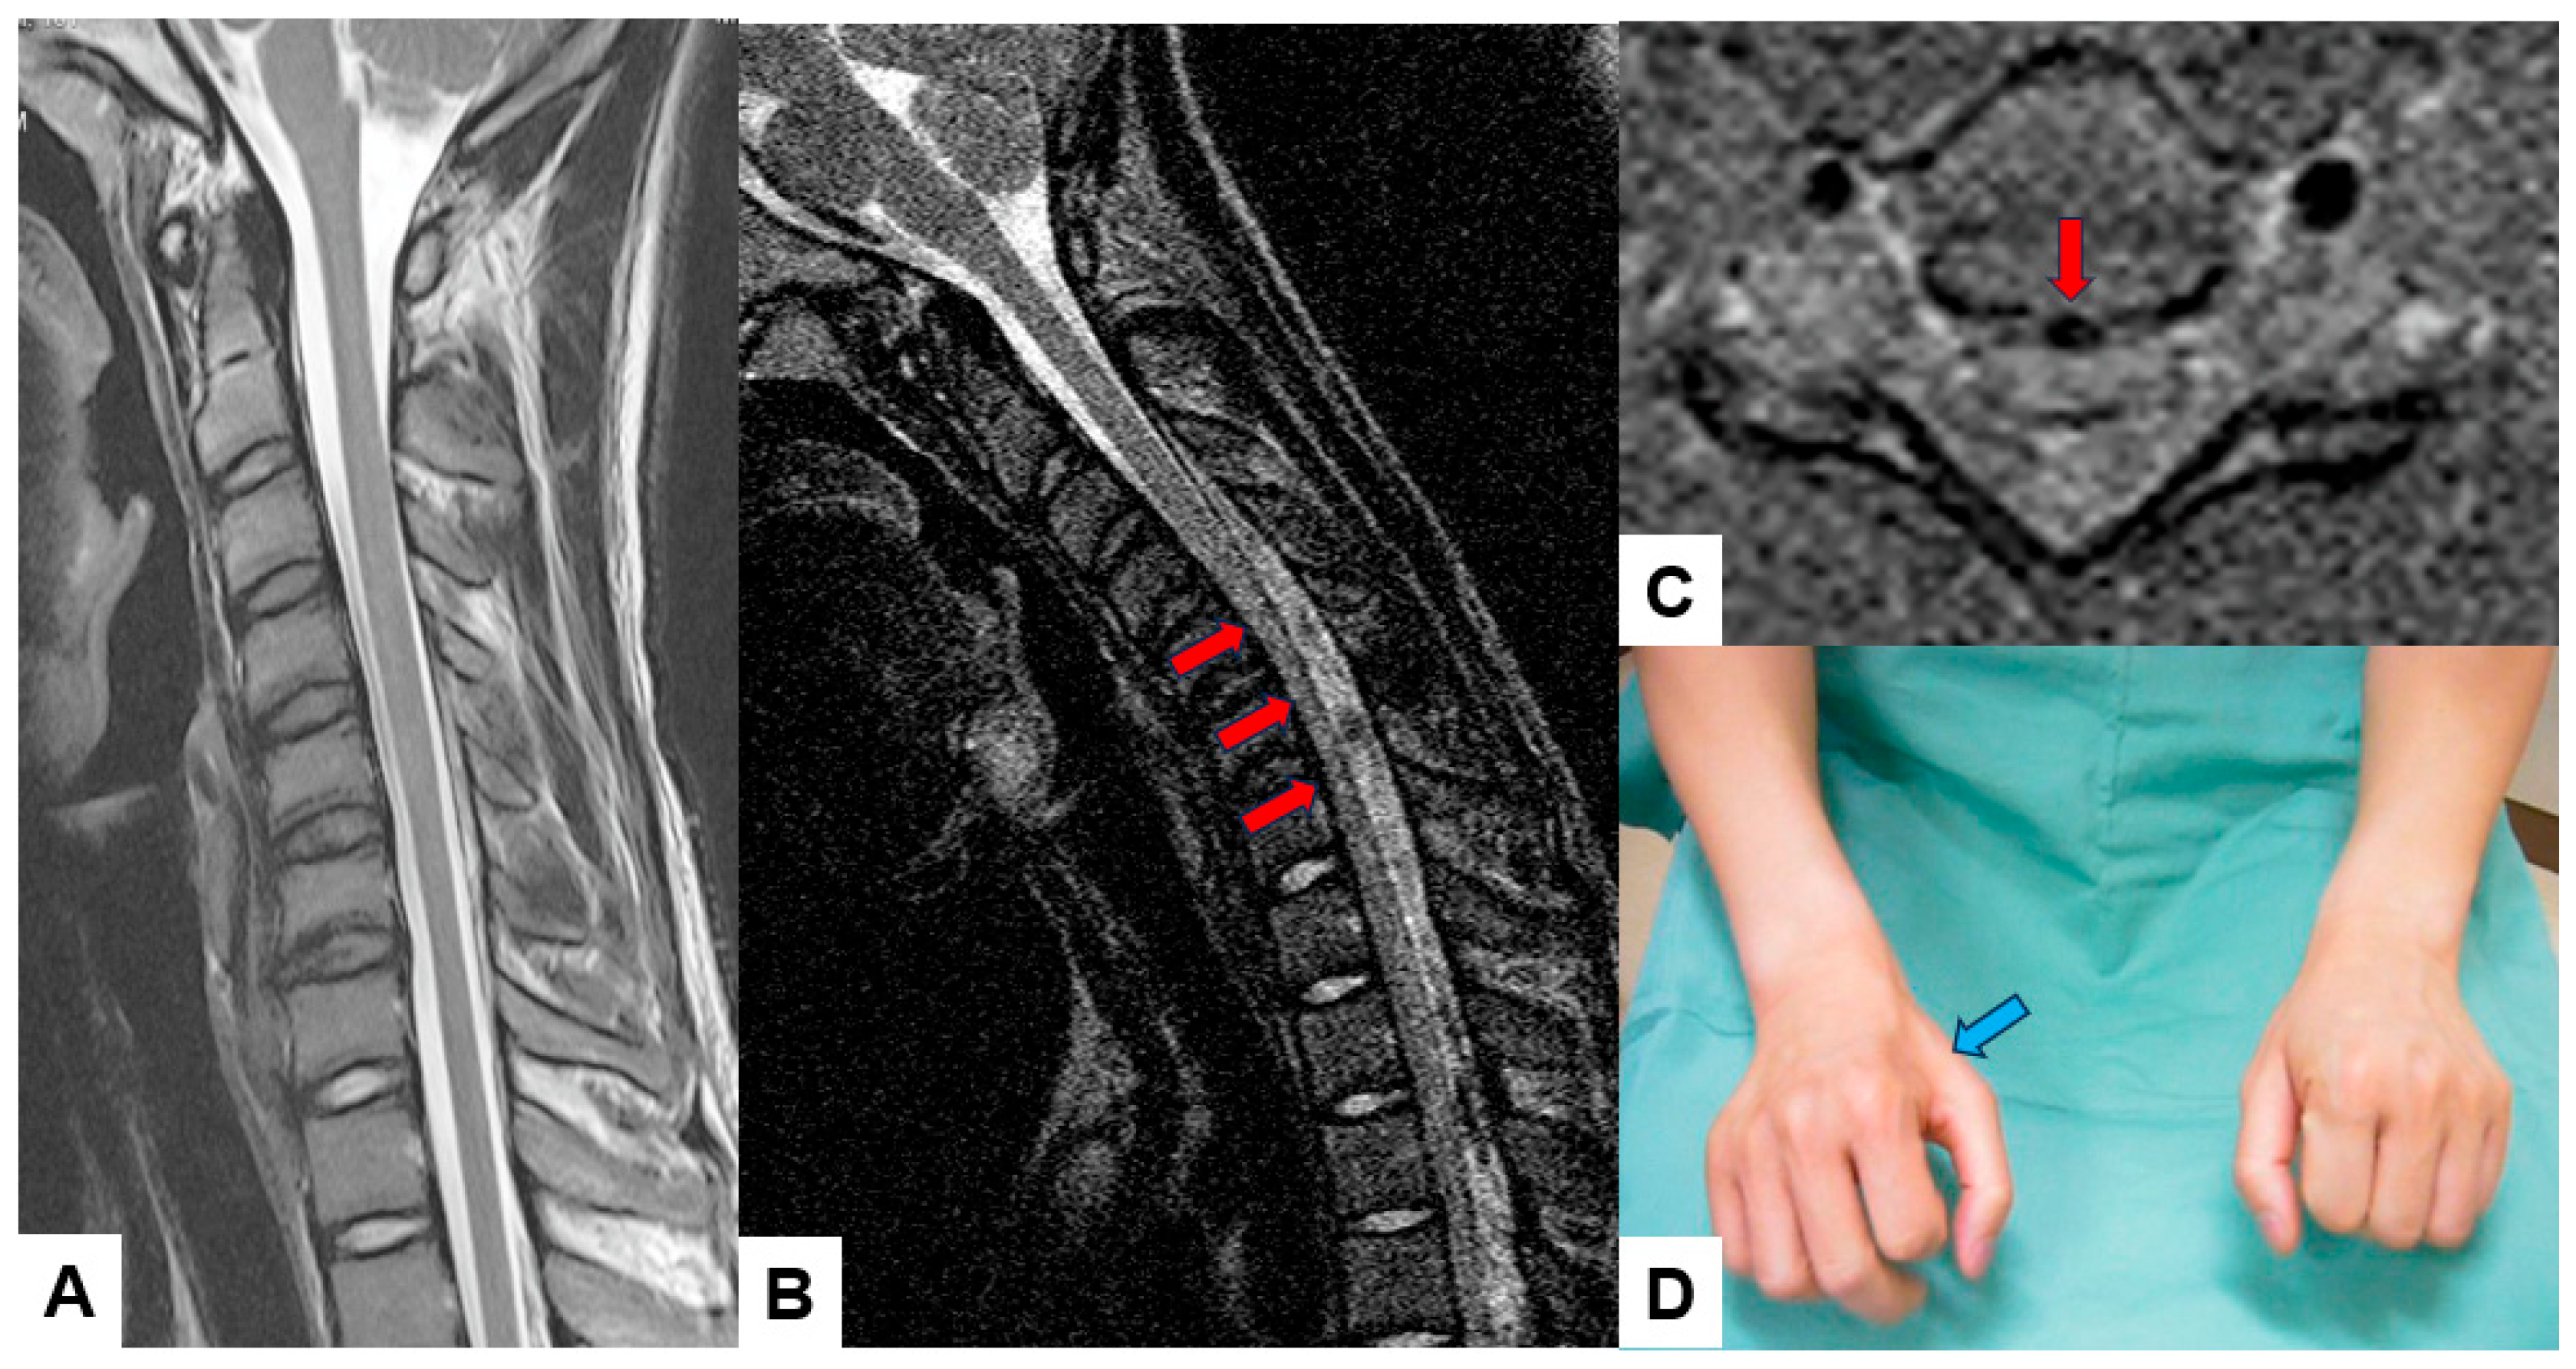

3.5. Upright and Kinetic MRI (Figure 7)

Traditional supine MRI remains the gold standard for evaluating spinal soft tissue, but weight-bearing or dynamic conditions are essential for spine pathologies. Therefore, this technique is developed to diagnose the full spectrum of spinal disorders, including inherent instabilities or positional nerve root compressions (Figure 7).

A vertically oriented magnet allows the patient to be scanned, standing, or seated. In contrast, kinetic MRI utilizes the same upright MRI machine with multiple dynamic or functional positions [58,59].

The main limitations of this imaging modality are the lower magnetic field strengths (0.5T–0.6T), which compromise the image resolution, longer exam duration, and motion artifacts [60].

Figure 7. Sixteen-year-old male, Hirayama disease, (A) cervical midsagittal T2-weighted MRI, (B) cervical midsagittal MRI in flexion position, (C) cervical axial T2-weighted MRI at C5/6, (D) bilateral hands of the patients. Red arrows indicate spinal cord compression in the flexion position. A blue arrow shows muscle atrophy in his right hand.